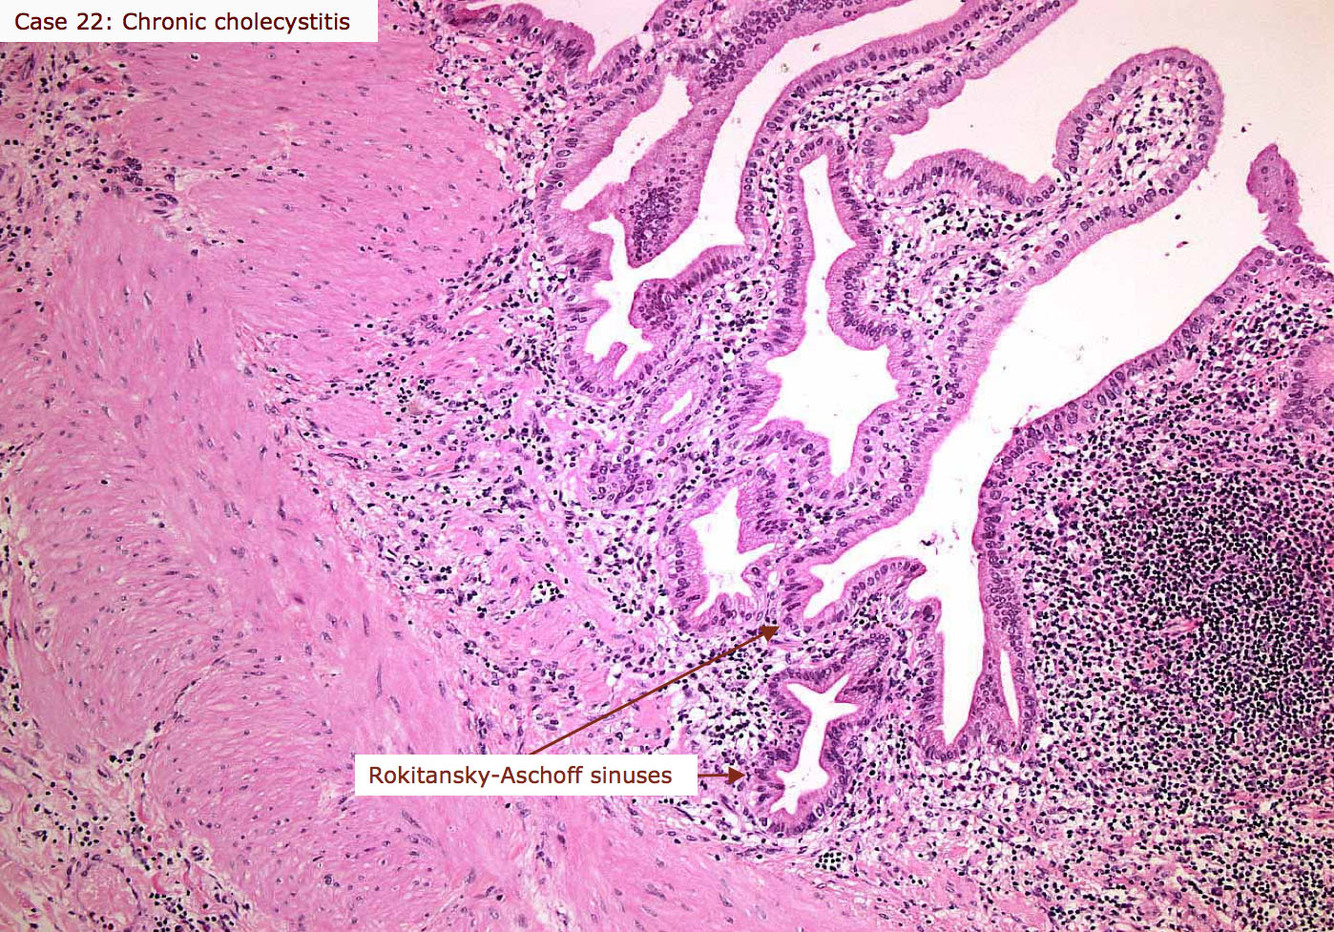

Histologic feature of chronic cholecystitis

Chronic GB inflammation causes formation of Rokitasky-Aschoff sinuses = pseudodiverticula, basically inpouchings/pockets in the GB wall

-not dagernous on their own, but can indicate chronic cholecystitis